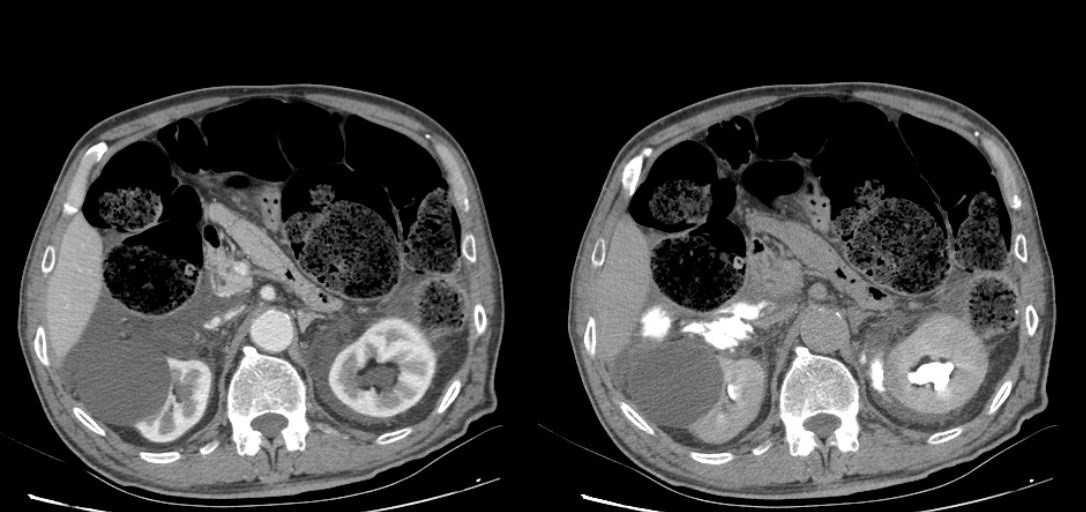

Figure 2.

Figure 2 and 3. As seen on the scans to the left, the surrounding free fluid dif. dx can mean urine, blood. On the scans to the right, the contrast media leakage is evident in the surrounding tissue, meaning there are lesions in the renal pelvis bilaterally.